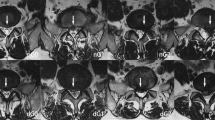

After surgical resection, the lumbar intervertebral disc tissue was fixed with 4% formaldehyde, embedded in paraffin, and sliced continuously at 4 μm. After the sections were deparaffinized and hydrated, they were immersed in 0.01 mol/L sodium citrate buffer (pH = 6) for autoclaved antigen retrieval. After rinsing, the sections were incubated in 3% hydrogen peroxide for 15 min and then incubated with 5% bovine serum albumin blocking solution at room temperature for 15 min. The primary antibody (83506, Cell Signaling, USA) was diluted 1:150, the sections were washed and incubated with the primary antibody overnight at 4 °C, and then they were washed and incubated with the secondary antibody at room temperature for 15 min. After washing, DAB reagent was added to the slices and incubated at room temperature for 3 min. Then, the sections were counterstained with hematoxylin for 5–10 s, and after repeated soaking and washing, ethanol gradient dehydration, xylene transparency and sealing were performed. Finally, the Aperio system (Leica) was used to observe the slices, in which 5 typical areas were randomly selected to manually count the number of positive cells (400 times magnification). The results of immunohistochemical staining were evaluated by the percentage of positive cells. The positive LC3B signal was defined as brown/yellow-brown in the cytoplasm or cell membrane. For each patient, 3 typical areas were randomly selected from a slide (magnification of 400×). Score based on the proportion of positive cells: (1) 1 point, < 10% of cells stained positive; (2) 2 points, 10–25% of cells stained positive; (3) 3 points, 26–50% of cells stained positively; and (4) 4 points, > 50% of cells stained positively (Fig. 3).

To further compare the autophagy intensity, we defined 1 point and 2 points as the low expression group and 3 points and 4 points as the high expression group. All evaluations were conducted by two independent, blinded evaluators to ensure reproducibility and accuracy. In cases of disagreement, the final grade was determined through consensus discussion.